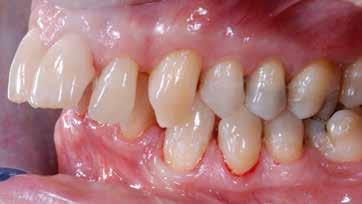

Figg. 229,230 > Impronte di precisione superiore e inferiore (fasi di laboratorio).

Fig. 231 > Modelli in gesso.

Fig. 232 > Realizzazione del modello master con monconi sfilabili in materiale refrattario.

Fig. 233 > Mascherina in silicone per determinare volumi dentali.

Figg. 234,235 > Ceratura diagnostica (CDT Romeo Pascetta).

Figg. 236,237 > Faccette in ceramica feldspatica.

Fig. 238 > Fase della cementazione.

Fig. 239 > Dettaglio dell’arcata superiore post-cementazione.

Figg. 240,241 > Immagine intraed extra-orale frontale postcementazione.